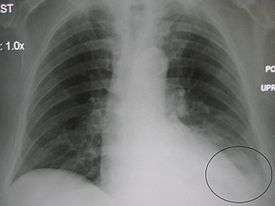

| A chest X-ray showing a very prominent wedge-shape bacterial pneumonia in the right lung. | |

AP CXR showing right lower lobe pneumonia

Right upper lobe pneumonia as marked by the circle.- Left upper lobe pneumonia with a small pleural effusion.